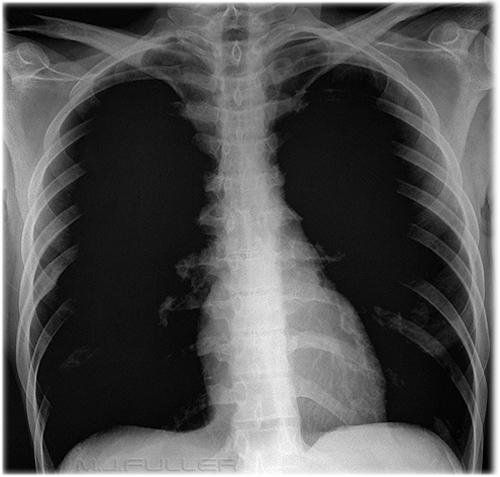

نضع بين ايديكم مجموعة الصور الاضافية على السلايدات التي تم شرحها في X-ray session :

pneumothorax

Hydrothorax

Pneumonia